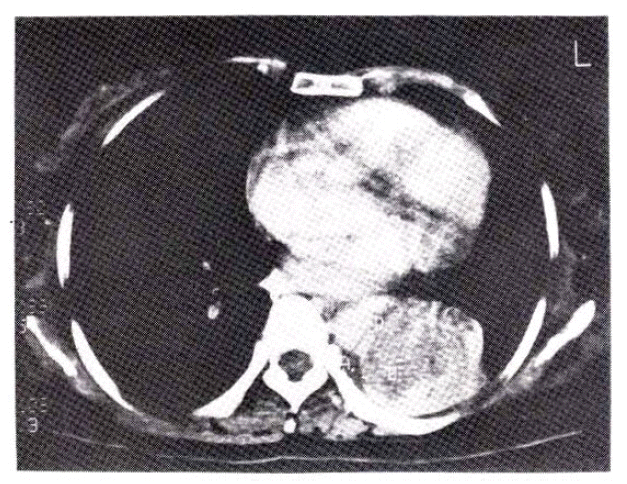

Five weeks before admission she began to cough up blood-streaked sputum. In a recumbent position she suffered from mild dyspnea and wheezing respiration intermittently. Ten days before admission she coughed up frank blood. At the time of admission, the physical examination revealed wheezing and decreased breath sounds in the left lower lung field. Mucocutaneous lesions and palpable lymph nodes were not present. Chest roentgenogram showed left lower lobe collaps (Fig. 2). Laboratory data were normal except for lactic dehydrogenase (LDH) of 414 IU/L. Liver scan was normal. Four repeated sputum cytologic examinations were negative for malignant cells. Pulmonary function tests showed a moderate restrictive pattern. On bronchoscopy, a fungating, dark grayish, irregularly surfaced endobronchial mass at the orifice of the left lower lobe bronchus nearly completely occluding the lumen (Fig. 3) was found. Bronchoscopic biopsy revealed metastatic malignant melanoma (Fig. 4). Computed tomography of the chest showed left lower lobe collapse and aortic invasion (Fig. 5). So palliative chemotherapy with dimethyl triazeno imidazole carboxamide (DTIC) was given as a five day schedule and she was discharged.

Fig. 2.

Postero-anterior view of the chest showing left lower lobe collapse